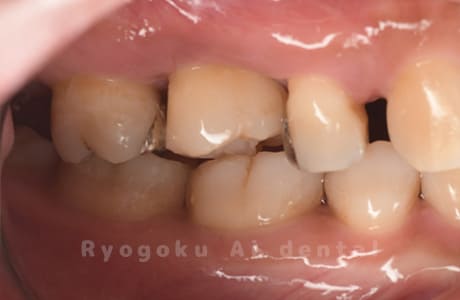

Case11

- 重度カリエス

- 治療内容

- 自家歯牙移植

- 治療期間

-

- 220,000円

歯が欠けたとのことでご来院された患者様です。虫歯が大きく、保存不可能と判断し、親知らずの移植を行いました。経過良好で、ご本人様も満足されております。